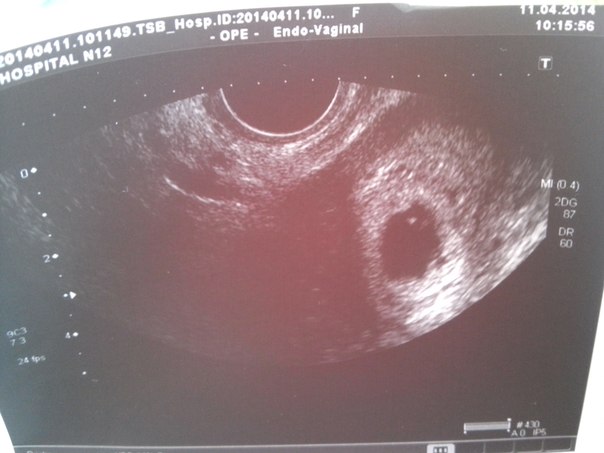

На первом снимке есть что-то в яице, не спешите с чисткой!!!!у меня была 3 недели задержки и я смотрела на узи там ничего не было только хгч показал маленькие результаты,которые начали расти!)и оказалась что это была поздняя овулька и нам тогда только 2 недельки было от зачатия,все потому что цикл не постоянный))и врач потом сказала что это дисфункция яичников,а сейчас все хорошо и мы развиваемся))))да и тогда когда искала причину почему не видят эмбриона поехала в боткинскую-там сделали узи и сказали что это вообще замершая,но нам дали снимочек,я вышла и моя мама сказала:что вот посмотри в яйце точечка,это ваш малыш и не плачь!!!)надо верить в лучшее,вы его так ждали!!)я поверила и через 3 недели наше сердечко за стучало))))все будет хорошо надо только верить!!!)

спасибо за поддержку) это первый снимок, а вот на последнем, т.е на пред последнем та тоже что то есть, но врач сказала что не понимае что, скорее всего замершая беременность(

Хгч более чем! Конечно, уже дб эмбрион. Сходите к другому узисту. А предыдущие хгч? По-моему все там видно

Александра

Плодное яйцо видно,но эмбриона я там не вижу.Я не врач,конечно.Но деформированное плодное яйцо не очень хорошо.А ХГЧ очень высокий.Вы к врачу ходили?К гинекологу?

Это по месячным? Если да, то у меня на этом сроке тоже эмбрион не видели. И тут много таких. Но у меня яйцо было недеформировано